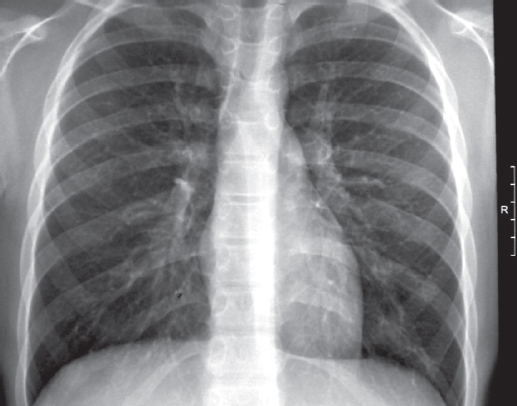

According to scientific research, malignant neoplasms in children are biomedical risk factors for the development of tuberculosis (TB). On the contrary, the occurrence of oncological disease in a child against the background of an existing tuberculous process is extremely rare. The combination of malignant neoplasm and tuberculosis creates difficulties in differential diagnosis, treatment of diseases, prevention of exacerbations and relapses. This article presents a clinical observation – the development of acute lymphoblastic leukemia (ALL) in a 6-year-old child against the background of TB of the intrathoracic lymph nodes during treatment. TB proceeded favorably despite multiple family contact in the child and resistance of Mycobacterium tuberculosis to anti-tuberculosis drugs in adult relatives of the patient. At the onset of ALL, bilateral pulmonary infiltrates and pleural effusion were observed, which were not associated with TB. Specific polychemotherapy for ALL and continued chemotherapy for TB led to the cure of two diseases. Supportive cytostatic and immunosuppressive therapy for ALL required periodic courses of anti-relapse anti-tuberculosis therapy for 5 years. After 10 years of observation, the child is healthy. Thus, the possibility of a rare in clinical practice combination of TB and ALL in children should be taken into account in the diagnosis and treatment of these diseases. During courses of immunosuppressive therapy for ALL, there is a risk of reactivation of TB. It is necessary to recommend long-term observation of such children by a phthisiatrician and an oncologist to prevent recurrence of both diseases.